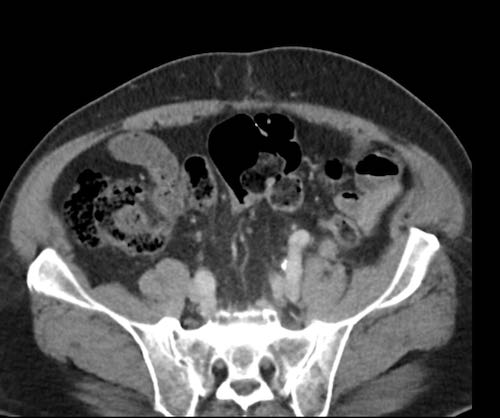

Ca lâm sàng 2

Cuộn qua các lát cắt.

Bạn có thể phát hiện tất cả các tổn thương cấy ghép phúc mạc không?

.jpeg)